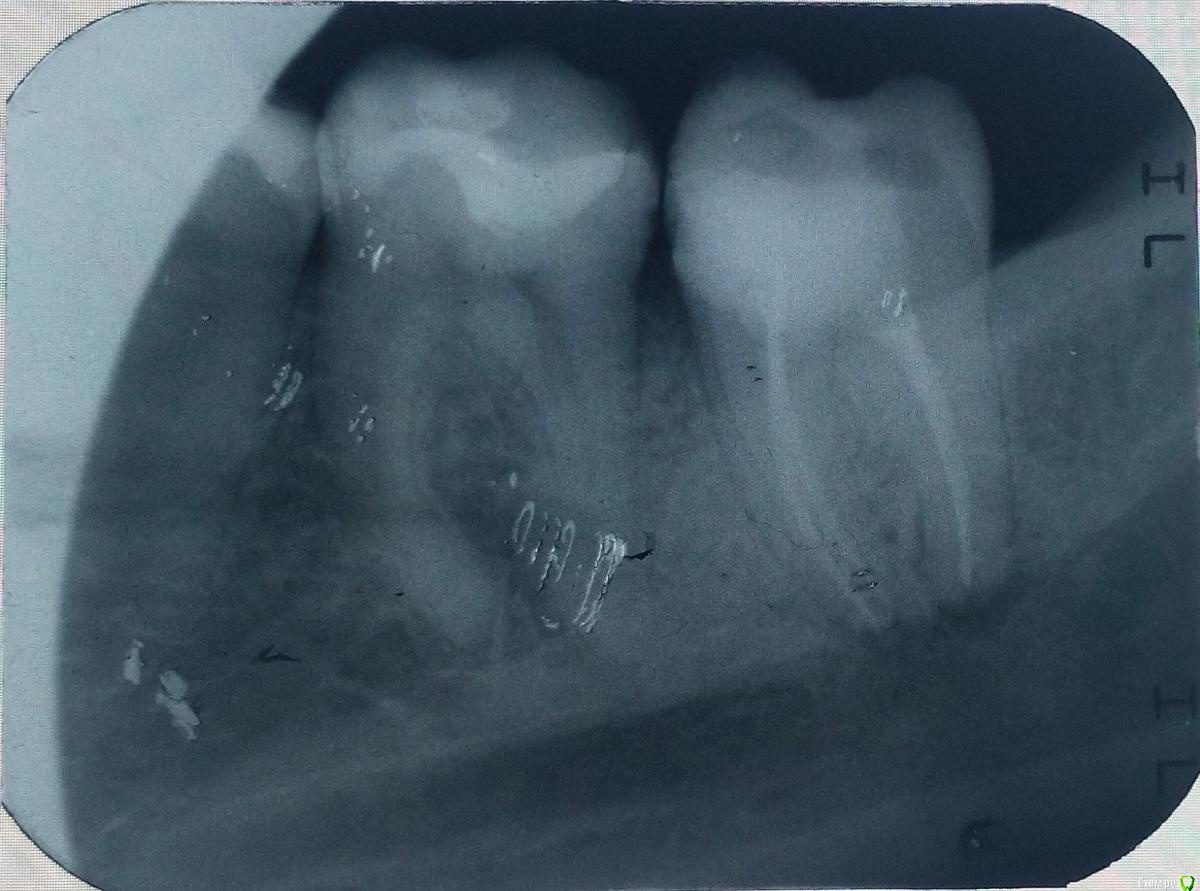

sergemiko Опубликовано 20 февраля, 2018 Поделиться Опубликовано 20 февраля, 2018 (изменено) Добрый день. Планирую ставить брекеты (на 2 года, самому 27 лет, муж.), но для полной красоты не хватает 12 зуба. Врач предложил сместить брекетами зубы друг к другу, либо, наоборот, раздвинуть для импланта на место отсутствующего 22 и коронки под 12 зуб. Вот, хочу посоветоваться, как лучше поступить.18 и 28 зубы уже удалены, собственно, я думаю, именно они, прорезываясь, сместили зубы в кривизну, но брекеты я решил ставить ещё до этого.37 зуб сделал доп.снимок, который показал, что воспаление не ярко выражено как на панорамном снимке, решили его не трогать.PS: немного смущают дёсна, кажется что оголились или это норма? Изменено 20 февраля, 2018 пользователем sergemiko Ссылка на комментарий